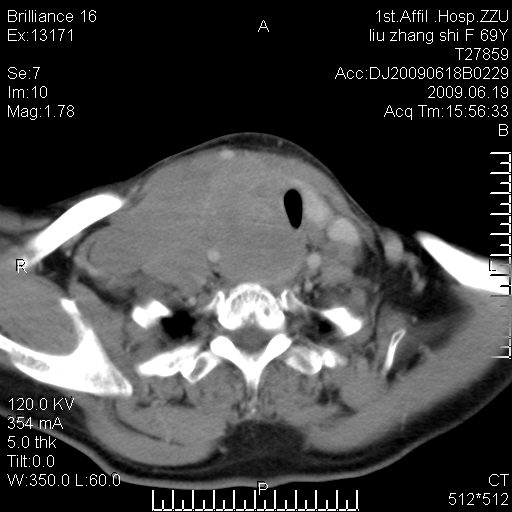

标题: CT26782:女,69岁,颈部占位,3天后公布病理结果。

【病理证实系列】女,69岁,颈部占位,有病理结果,3天后公布。(由于病例时间较久,临床资料不全,请网友见谅)本系列将有几百种常见、少见及罕见病例,均经病理证实。病例资料来自郑州大学第一附属医院。与网友共享,本人有空就发。

甲状腺癌并颈部淋巴结转移。感谢楼主的良苦用心,谢谢。

甲状腺癌并颈部淋巴结转移。

需与鼻咽癌鉴别!

支持甲状腺癌广泛侵及周围结构并颈部淋巴结转移。

鉴别:淋巴瘤、恶性神经源性病变、恶性纤维组织细胞瘤。

病理结果:颈部非霍奇金淋巴瘤。

右侧甲状腺确实有问题